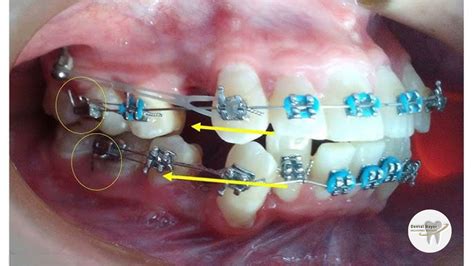

Los elásticos intraorales se pueden colocar sobre los brackets en caso de ortodoncia convencional o sobre los botones en caso de alineadores.

- Para cerrar el espacio entre los dientes: se colocan desde el primer o segundo molar superior hasta el gancho de la cúspide superior.

- En maloclusiones de clase 2, para reforzar el anclaje en caso de haber realizado una extracción, para permitir que los incisivos maxilares se muevan hacia atrás o para corregir la desviación de la línea media y permitir el movimiento bucal de los incisivos inferiores con punta hacia atrás: en estos casos se utilizan desde el primer molar inferior hasta el diente canino superior.